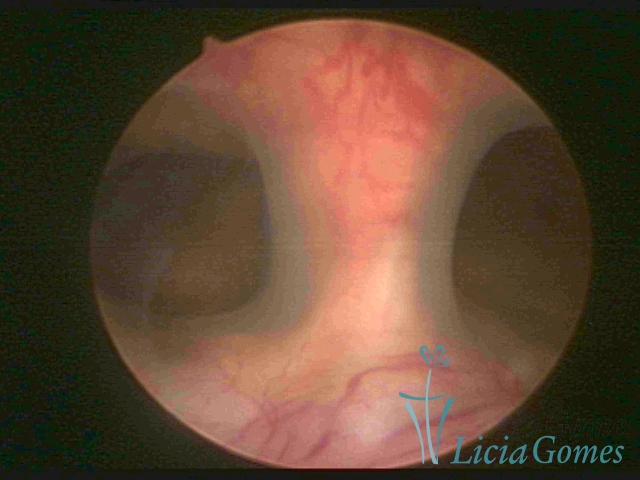

Septate uterus

It probably occurs by the lack of resorption on the middle line, in the merge of Müllerian ducts. The uterus is divided by a partial or total septum which is viewed as a crossbar, not covered by endometrium, which not bleeds when sectioned.

Complete septum when it occupies the whole extension of the cavity, dividing it into two hemicavities.

When this septum occupies only a part of the extension of the uterine cavity, it is considered as incomplete.